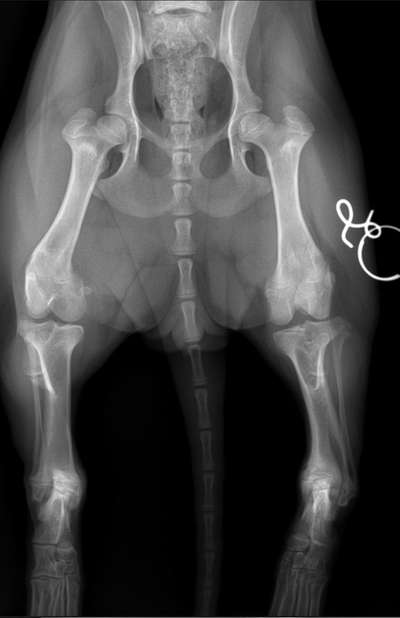

Unsere 5 Monate alte Hündin hat im Hinterlauf eine diagnostizierte halbseitigen Verschluss der wachstumsfuge. Aktuell zeigt sich das beim laufen so, das es einseitig wirkt, als hat sie ein O-Bein. Die Muskulatur ist schwächer ausgeprägt als auf der anderen Seite und sie wird wackeliger wenn die Spaziergänge länger werden. Es kann auch mal bei Raufen mit anderen Hunden dazuführen, dass sie kaum Gefühl im Fuß hat und es einige Minuten braucht. Die Op hätte es in sich. Vollnarkose und ein Stück Knochen würde entfernt werden…. Mir macht das Angst. Geht das nicht auch anders?

Hallo Mona, Diese Erkrankung gibt es sowohl im Bereich der Vorder- als auch der Hintergliedmaßen und betrifft vor allem sogenannte chondrodystrophe Hunderassen, wie Dackel, Pekinesen oder Französische Bulldoggen. Anhand des Röntgenbildes liegt vermutlich eine Wachstumsstörung im gelenknahen Bereich des Schienbeinknochens der linken Hintergliedmaße vor. Die untere Wachstumsfuge schließt zu frühzeitig. Diese Wachstumsfuge ist maßgeblich entscheidend für ein ausreichendes Längenwachstum des Knochens. Ist sie geschlossen, ist das Längenwachstum vermindert. Das Wadenbein wächst dabei aber normal weiter in die Länge. Aufgrund der mangelnden Knochenhärte im Welpen- und Junghundealter kommt es zur Biegung des schneller wachsenden Knochens, sprich des Wadenbeins. Durch eine frühzeitige Operation des Schienbeins (an der Wachstumsfuge) kann die Fehlstellung der Gliedmaße einfach verbessert werden. Sind die Tiere bereits ausgewachsen, ist eine kompliziertere kombinierte Operation von Schien- und Wadenbein notwendig, in der versucht wird die Achsenabweichung zu korrigieren. Demnach ist es besser und sinnvoller die Tiere so früh wie möglich operieren zu lassen, bzw. sobald die Wachstumsstörung festgestellt wird. Es gibt verschiedene OP-Methoden, welche je nach Drehung der Pfote und Stufenbildung der Knochen individuell vom Chirurgen festgelegt werden. Alternativen gibt es leider nicht, da das Wachstum nur eines Knochens medikamentös nicht beeinflusst werden kann. Je älter die Hunde sind, umso schwieriger die Korrektur und umso langsamer verhält sich das Knochenwachstum und die Heilung. Außerdem kann es ohne OP mit zunehmendem Alter aufgrund der Fehlbelastung zu frühzeitigeren Arthrosen und zunehmendem ein- bis beidseitigem Muskelabbau kommen.